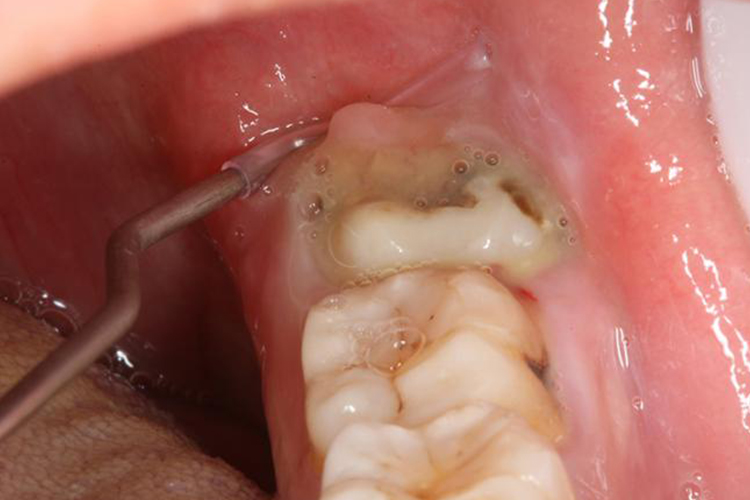

智齿冠周炎:急性智齿冠周炎末期未彻底治愈可转变为慢性过程,临床表现为冠周软组织轻度水肿,龈袋内可有少量脓性分泌物,出现溃烂。如果发生在面颊部可有慢性瘘管形成,瘘管口会有红色的肉芽组织,全身可伴有低热。